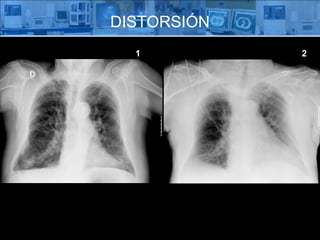

¿ QUÉ ES  ? Distorsión Radiológica Es la representación errónea del tamaño y la forma de un  objeto en la radiografía .

DISTORSIÓN Elongación: aumento de tamaño. Acortamiento: disminución del tamaño.

DISTORSIÓN 1 2

DISTORSIÓN ELONGACIÓN DEL CORAZÓN 1 2